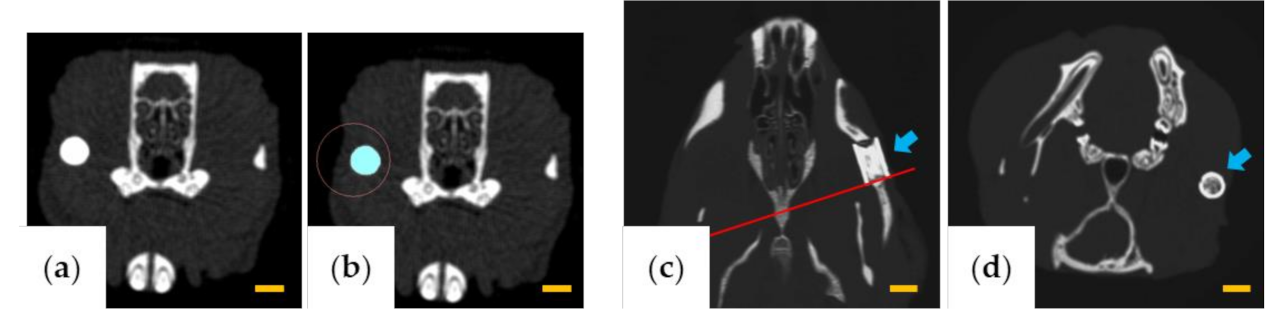

The volume of β-TCP was measured using LaTheta software v.3.50 (Hitachi Aloka Medical, Tokyo, Japan) by designating the β-TCP portion as the region of interest for each slice (Figure 2a,b). The β-TCP residual rate (%) was calculated from the volumes at 1 month, 3 months, and 6 months, assuming that the volume of β-TCP was 100% immediately after implantation.

To evaluate the change of the cross-sectional area of β-TCP, AZE Virtual Place Lexus 64 was used to reconstruct the image of the rear edge of β-TCP in a plane perpendicular to the through-and-through holes (Figure 2c,d). Six months after implantation, the area of β-TCP was measured using ImageJ software v.1.52 (National Institutes of Health, Bethesda, MD, USA) and was calculated as a percentage relative to the area in a cross-section before implantation.

Figure 2. Images for measuring the β-tricalcium phosphate (TCP) volume and β-TCP cross-sectional area. (a,b) Images used for volume measurement. (a) Computed tomography (CT) image of the area containing β-TCP and (b) designation of the region of interest. (c,d) Images used for cross-sectional area measurement. (c) β-TCP long-axis plane (red line indicates the rear end position). (d) Plane perpendicular to the through-holes at the position of the red line in (c). The arrows indicate β-TCP. Scale bars = 3 mm.